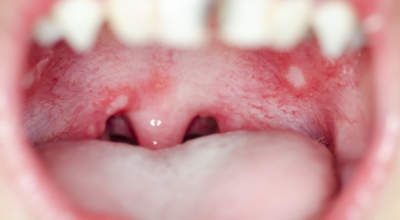

구내염이란

구강에 나타나는 통증을 동반하는 염증성 질환을 통틀어 구내염이라 해요. 그러나 구강의 점막에 나타나는 질환들은 다양하면서도 병변의 모양이 서로 비슷해서 감별진단에 어려움이 있기 때문에 세심한 병력청취와 관찰이 필요해요.

구내염은 증상별, 발생 부위별, 이유가 되는 것별, 이학적 검사 소견에 따른 여러가지 분류법들이 있으나 각 질환에 대하여 일률적으로 적용하기는 곤란해요. 그러므로 대부분 이들의 여러 분류법들을 혼합해서 분류하는 경우가 많으며, 보통은 구내염은 궤양성 구내염, 수포성 구내염, 미란성 구내염으로 나뉩니다.

구내염 원인 - 바이러스성 구내염

바이러스로 인해 나타나는 구내염도 있습니다. 단순 헤르페스 바이러스의 감염 원인의 '헤르페스성 구내염'은 주로 타액 과 같은 접촉으로 인하여 감염됩니다. 또 곰팡이의 일종인 칸디다균은 원래 입안에 존재하는 상재균의 한 개지만, 만약 면역력이 저하되면 증식해서 '칸디다성 구내염'을 병이 발생하게 되어요. 바이러스성 구내염에 많이 관찰되는 다발성 구내염은 입 점막에 많은 소수포가 형성되어 찢어져 붕괴를 나타나게 할 수이 있고 발열이나 엄청난 통증이 수반될 수 있습니다.